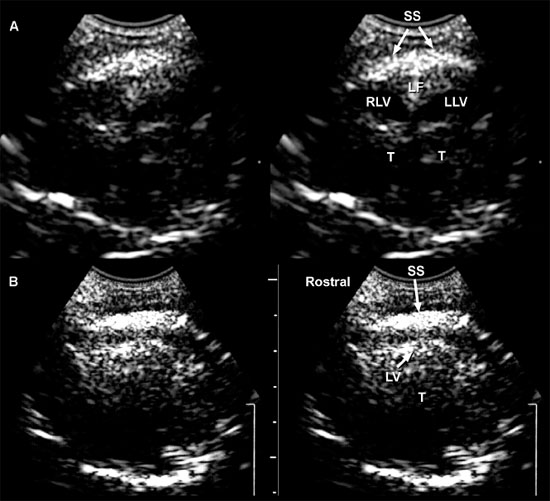

The sonographic anatomy of the brain of normal dogs has been described (Hudson et al. 1989) (Figure 1.3). The longitudinal fissure and splenial sulci form a hyperechoic umbrella-like structure that can be used as a landmark to locate the midline of the brain. This is particularly useful when a natural or created defect in the skull is located asymmetrically. The cingulate gyrus is found deep to each splenial sulcus. Rostrally, the caudate nuclei are recognizable as hyperechoic curved structures. The lateral ventricles are located medial to the caudate nuclei and vary greatly in size according to the breed, age, and individual. Asymmetry is common. Cerebrospinal fluid (CSF) is anechoic and may cause the lateral ventricles to appear as small anechoic slits in some individuals.

Figure 1.3. Transverse sonograms of the brain of a 1-month-old Yorkshire terrier. The ventricles are asymmetrical but within normal limits. A: Rostral sonogram. B: Sonogram at the level of the interthalamic adhesion. C: Sonogram at the level of the third ventricle. D: Sonogram with the ultrasound beam angled caudally to image the mesencephalon. E: Sonogram with the ultrasound beam angled caudally to image the cerebellum. 3, third ventricle; CC, corpus callosum; CG, cingulate gyrus; CN, caudate nucleus; F, fornix; H, hippocampus; IA, interthalamic adhesion; LF, longitudinal fissure; LLV, left lateral ventricle; M, mesencephalon; P, pyriform lobe; Po, pons; RLV, right lateral ventricle; SS, splenial sulcus; Su, subarachnoid space; T, thalamus; and V, vermis.

As the beam is swept slightly more caudally, the rostral fornix comes into view. Choroid plexus is hyperechoic while it lies on the floor of the central portion of the lateral ventricle and the roof of the temporal horn. It may be difficult to distinguish between the caudate nucleus and the adjacent choroid plexus in the lateral ventricle, so only a single hyperechoic focus might be seen on each side of the midline in some dogs. If there is sufficient CSF, the lateral ventricle can be seen.

In older puppies and adult dogs, alternating hyperechoic and hypoechoic lines represent the callosal sulcus, corpus callosum, and fornix. Comparison with histological samples suggests that the most superficial hyperechoic layer is the callosal sulcus, which contains vessels that pulsate. The corpus callosum is comprised of a hypoechoic surface with a deeper hyperechoic border. The fornix is hypoechoic. In the first few days of life, these structures may appear only as a single hyperechoic region. Detail improves as myelination progresses after birth. Most of the brain is uniformly hypoechoic, but the pyriform lobes are visible because of hyperechoic meninges dorsal to each lobe.

When the probe is tilted to sweep the ultrasound beam caudally, the dorsal portion of each hippocampus appears as a hypoechoic structure close to the midline. Dorsolateral to each of these structures, a hyperechoic area represents choroid plexus in each lateral ventricle. Another hyperechoic area is seen in the midline ventral to the level of the dorsal portions of the hippocampi. Depending on the angle of ultrasound section, this hyperechoic area may represent choroid plexus in the dorsal portion of the third ventricle or pia mater that is located more caudally in the adjacent subarachnoid space. Vessels and trabeculae in the subarachnoid space may create a complex of echoes that outline the mesencephalon and cause it to appear as a dome-shaped hypoechoic structure. The petrous temporal bones will create irregular hyperechoic echoes on the floor of the cranium on each side of the midline deep to the hypoechoic pyriform lobes.

More caudally, the osseous tentorium is a hyperechoic structure shaped like an inverted V. In older animals, this structure often prevents visualization of the caudal brain, but the medulla and cerebellum can be imaged in neonatal animals. The medulla is hypoechoic. The vermis of the cerebellum is represented by a stack of hyperechoic lines seen in the midline. Each lateral cerebellar hemisphere is located more laterally as a hypoechoic structure.

Longitudinal images made near the midline are true sagittal images, but when the probe is moved past the edge of the fontanel, the probe must be angled to enable the beam to reach the lateral margins of the brain. The floor of the cranium appears curved in images showing the lateral portions of the brain, whereas the floor of the cranium is more irregular in images made near the midline (midsagittal images). As the probe is angled laterally, structures that are anatomically closer to the midline appear in the near field of the ultrasound image, whereas more lateral structures are seen in the far field (Figure 1.4).

The interthalamic adhesion and, more caudally, the mesencephalon can be seen in midsagittal images as hypoechoic structures surrounded by echoes created mainly by choroid plexus in the third ventricle and meninges and in vessels in the subarachnoid space. In some areas, the third ventricle will appear anechoic or hypoechoic because of the presence of CSF. The osseous tentorium is incompletely ossified in neonates, enabling visualization of hyperechoic echoes created by the vermis in the posttentorial area of the brain. More superficially, the callosal sulcus is seen as a hyperechoic line. The corpus callosum has an appearance similar to that seen in transverse images. It is hypoechoic, with a deep hyperechoic interface.

When the probe is angled to obtain a lateral parasagittal image, the subarachnoid space and third ventricle are no longer seen; the thalamus and lateral ventricle are now visible on the imaged side. The thalamus appears as a hypoechoic structure outlined by hyperechoic choroid plexus in the lateral ventricle. Areas of the lateral ventricle with sufficient CSF may appear anechoic or hypoechoic. The caudate nucleus is imaged rostral to the thalamus as a hypoechoic structure with increased echogenicity superficially. This structure is more apparent in older dogs than in neonates. The thalamocaudate groove is seen between the thalamus and caudate nucleus. This groove is more apparent in older dogs, but in neonates a hyperechoic clump of choroid plexus is often seen in the lateral ventricle in this region. Care should be taken not to mistake this normal appearance for intraventricular hemorrhage that is also hyperechoic. In lateral parasagittal images, the splenial sulcus is seen in addition to the callosal sulcus and corpus callosum and appears as an undulating hyperechoic line. The cingulate gyrus shows as a hypoechoic structure deep to the splenial sulcus.

Figure 1.4. Sagittal to parasagittal sonograms of the brain of a normal 1-month-old Yorkshire terrier. A: Midline sagittal sonogram. B: Parasagittal sonogram with the ultrasound beam angled laterally to image the right lateral ventricle. C: Parasagittal sonogram with the ultrasound beam angled laterally to image the left lateral ventricle. C, cerebellum; CG, cingulate gyrus; CN, caudate nucleus; F, fornix; H, hippocampus; IA, interthalamic adhesion; L, left; M, mesencephalon; R, right; RLV, right lateral ventricle; SS, splenial sulcus; and T, thalamus.